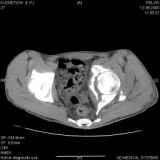

Уважаемые коллеги! Хотелось бы услышать совет по тактике лечения представлленого больного.

Поступил после лечения в одном изотделений области. Травма 2,5 месяца назад.

После выведения

из шока был произведен остеосинтез перелома бедра, предплечья, до перевода к нам проводилось

вытяжение по оси шейки бедра за стержень, введенный в большой вертел. На сегодня деформация

ригидна, клинически мобильности не определяется.